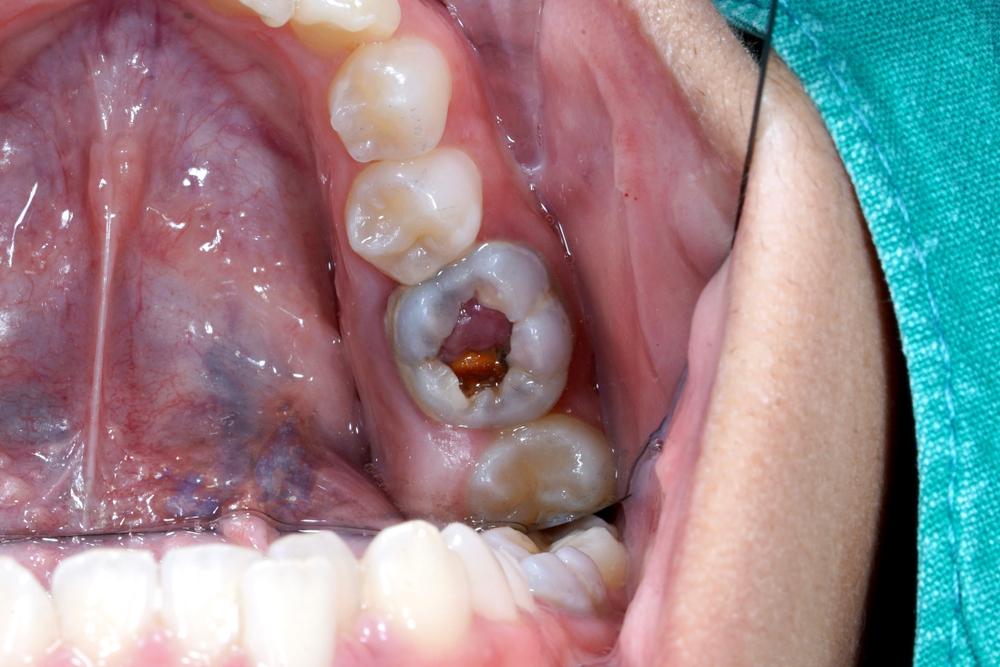

- Munculnya jaringan lunak dan kenyal (seperti daging) berwarna merah muda, putih, atau merah dari lubang gigi.

- Polip muncul pada gigi geraham karena memiliki ruang pulpa yang besar.

- Polip terus tumbuh dan baru berhenti saat memenuhi lubang gigi.